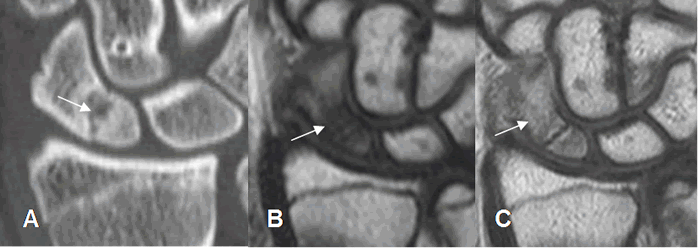

Fig 52 B. Seudoartrosis del escafoides.

A: Rx AP, B: TAC reconstrucción coronal y C: TAC reconstrucción sagital. Fractura del escafoides fijada con material de osteosíntesis. Se encuentra aumento del espacio entre los extremos, esclerosis de los bordes y ausencia de callo óseo, por la presencia de seudoartrosis. El polo inferior del escafoides es denso, por probable osteonecrosis. (Flechas gruesas).